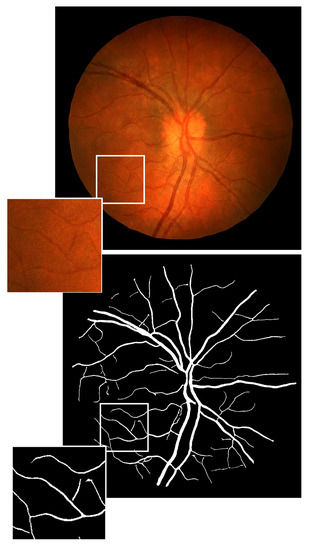

3.2. Vasculature Generation

3.3. Translating Vessel Maps into Retinal Images